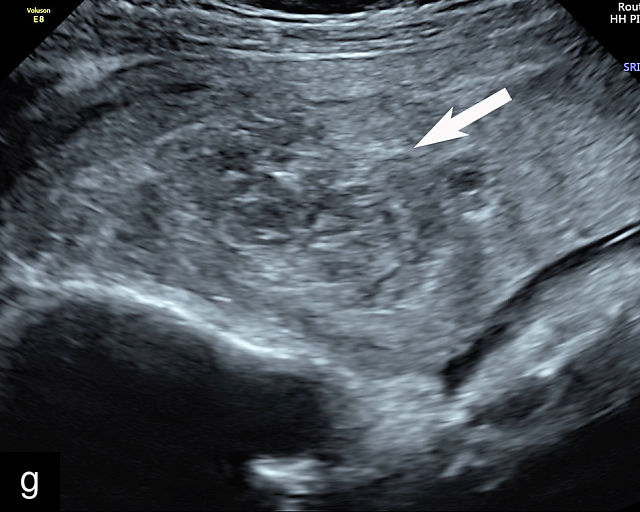

5

Placenta previa and low-lying placenta. (a) Transabdominal grayscale ultrasound image suspicious for placenta previa. The placenta (PL) appears to overlie the internal cervical os (CX). Note the time stamp: 2:19:37. (b) Transvaginal ultrasound of the same patient taken approximately 50 minutes later. Note the time stamp: 3:10:25. The internal os and the lower placental edge are both clearly seen, and the placenta does not overlie the internal os. Because the lower placental edge is 1.93 cm from the internal os, it will likely resolve by the third trimester. (c) Transabdominal grayscale ultrasound of placenta previa. The placenta (p) covers the cervix, but the cervix, especially the internal os, cannot be visualized due to shadowing. (d) Transabdominal grayscale ultrasound of placenta previa. The placenta (p) covers the cervix (c) but shadowing obscures adequate visualization. The internal os is indicated by the arrow. (e) False-positive image of placenta previa on transabdominal grayscale ultrasound. The bladder (b) is full, pushing the anterior and posterior walls of the lower uterine segment (ls) together making it appear that the placenta (p) overlies the internal os of the cervix. In reality, the line depicted by the arrowheads is where the anterior and posterior walls of the lower segment are in proximity to each other. The cervix is much lower and is obscured by shadowing (c). (f) Transabdominal grayscale ultrasound image of placenta previa. The placenta (p) covers the cervix (c), but the cervix, especially the internal os, cannot be visualized due to shadowing. b, bladder. (g) Transvaginal grayscale ultrasound image of placenta previa. The placenta (p) completely covers the internal os (arrow) of the cervix (c). The internal os can be seen clearly. h, fetal head. (h) Transvaginal grayscale ultrasound image of posterior low-lying placenta (p). The lower placental edge is clearly seen and is 1.56 cm from the internal os (arrow) of the cervix (c). The placental edge and the internal os are clearly seen. h, fetal head. (i) Transvaginal grayscale ultrasound image of a posterior placenta previa (p). The internal cervical os is clearly seen (arrow). c, cervix. (j) Transvaginal grayscale ultrasound image of an anterior placenta previa (p). The internal cervical os is clearly seen (arrow). c, cervix; h, fetal head. (k) Transvaginal grayscale ultrasound image of a posterior placenta that was thought to be low-lying on transabdominal sonography but could not be adequately assessed. This examination clearly shows the lower edge of the placenta (p) to be 2.18 cm from the internal os (arrow) of the cervix, firmly establishing that the placenta is not low-lying and allowing the patient to undergo labor safely and deliver vaginally. c, cervix. (l) Transvaginal grayscale ultrasound image of placenta previa. The placenta (p) completely covers the internal os (arrow) of the cervix (c). The internal os can be seen clearly.

This distinction is critical in determining the mode of delivery.49,51 All patients with placenta previa persisting into late pregnancy require cesarean delivery to avoid complications such as severe bleeding.50,60,61 Studies suggest that patients with a lower placental edge located more than 1 cm from the internal os may safely attempt a vaginal delivery without a significant increase in bleeding risk.68,69,70,71

Most cases of placenta previa will be suspected prenatally by transabdominal ultrasound.49 However, this approach has several limitations and may be inaccurate.72,73,74 because the relationship between the placenta and the internal cervical os may be difficult to assess by transabdominal ultrasound.72,73,74 The bladder may be full, pushing the anterior and posterior walls of the lower uterine segment together, falsely creating the impression of a placenta previa (Figure 5e).61 There may be considerable shadowing, including by the fetal presenting part, which may limit the accuracy of transabdominal ultrasound (Figure 5d,f).75 Posterior placentas may be more difficult to assess.

Transvaginal ultrasound overcomes these limitations (Figure 5g–l).72,73,74,76 The probe is inserted into the vagina and therefore is closer to the region of interest.51,61 In addition, transvaginal transducers have higher frequencies and superior resolution compared to transabdominal transducers. Transvaginal ultrasound is safe and is not associated with increased bleeding.72,73,74,75,76 As such, transvaginal ultrasound should be the imaging modality of choice whenever there is suspicion of placenta previa.49,67,77